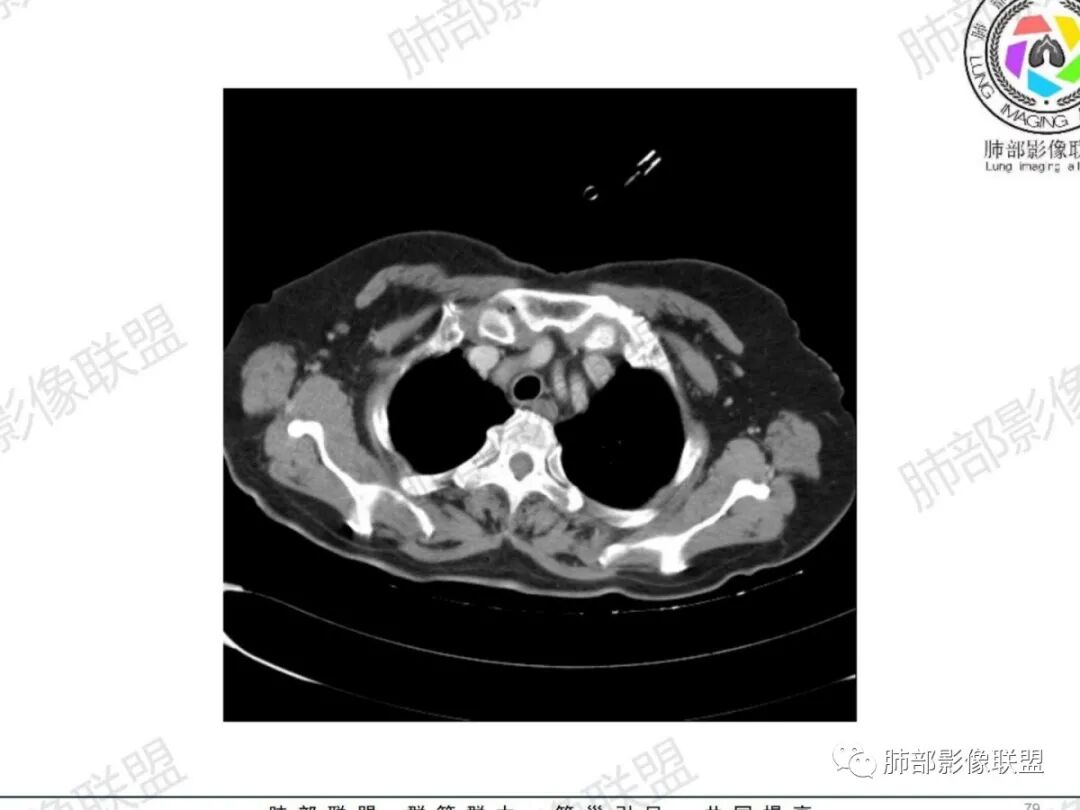

主支气管后缘外可见一实性结节,病变跨支气管管壁生长,部分突向管腔内,病变边缘光滑,平扫密度均匀,增强后尚均匀强化,纵隔淋巴结肿大不明显。

气管右后侧壁结节,结节向气管腔内突出,气管壁增厚,轻度强化,左侧甲状腺占位,考虑气管原发肿瘤,腺样囊性癌?类癌?

1.定位:软骨中断,非外压,而是气管本身起源,考虑恶性。与之鉴别是周围间叶起源的神经源性或平滑肌起源良性肿瘤

气管右后壁占位,平扫密度稍低于肌肉

增强后与肌肉类似,部分强于肌肉,提示强化

内外边缘光滑

宽基底与气管相连

附近壁增厚

前方见一小淋巴结,后内侧与食道联系很紧

宽基底,腔内外,看似边界清楚、光滑, 但是附近气管壁增厚,还是首先要考虑恶性,附近淋巴结也不太放心,因为强化明显